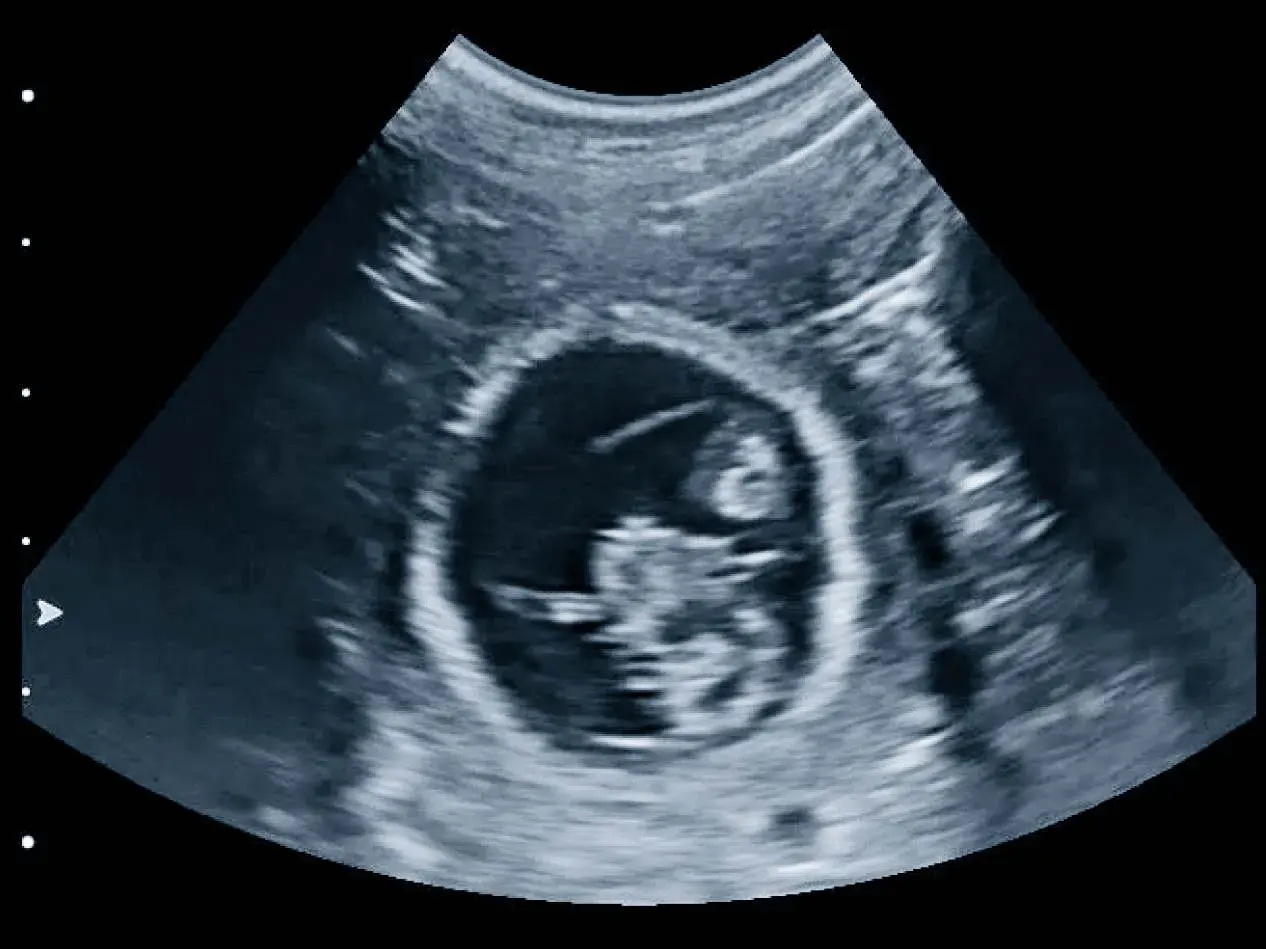

Ultrazvučna pretraga je važan dijagnostički alat u veterinarskoj medicini jer omogućuje veterinarima da dobiju detaljan uvid u unutarnje strukture tijela bez potrebe za invazivnim postupcima.

Tijekom ultrazvučne pretrage dio tijela je izložen bezopasnim, visokofrekventnim zvučnim valovima kako bi stvorio slike unutarnjih struktura tijela na ekranu uređaja.

Tako uživo možemo vidjeti kretanje, funkciju i strukturu unutarnjih organa vašeg ljubimca.

UZV se koristi u svrhu dijagnostike bolesti svih organa trbušne šupljine, srca i krvožilnog sustava.